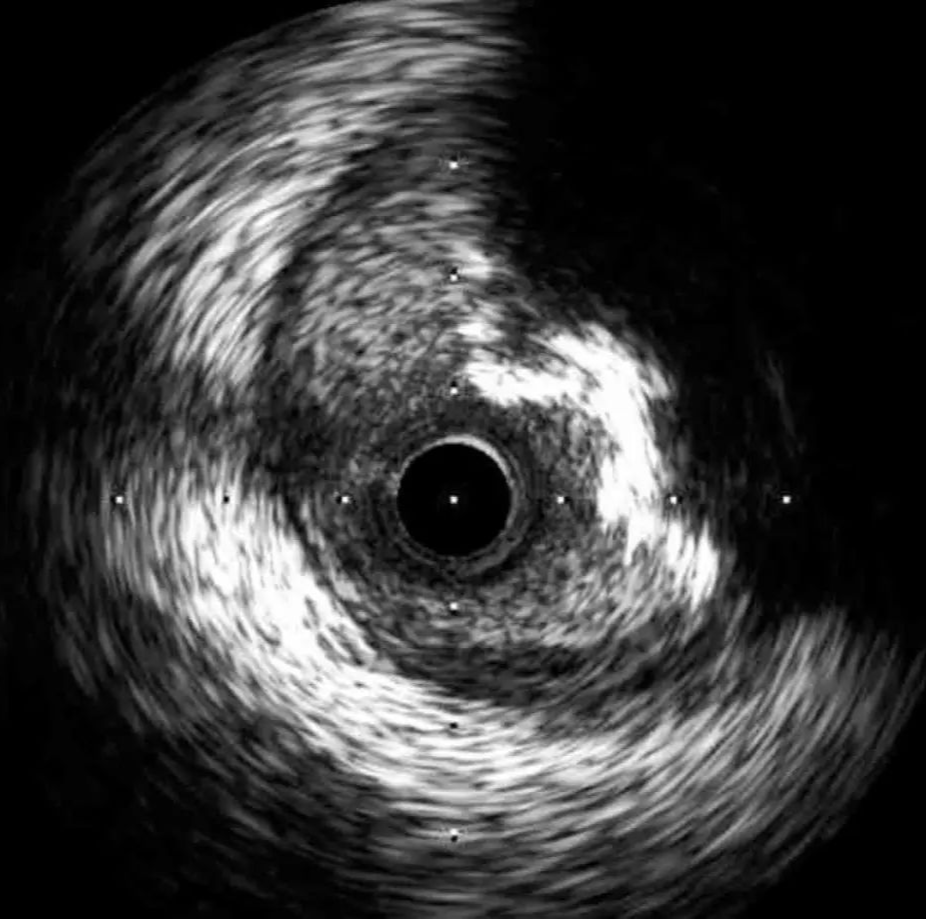

IVUS